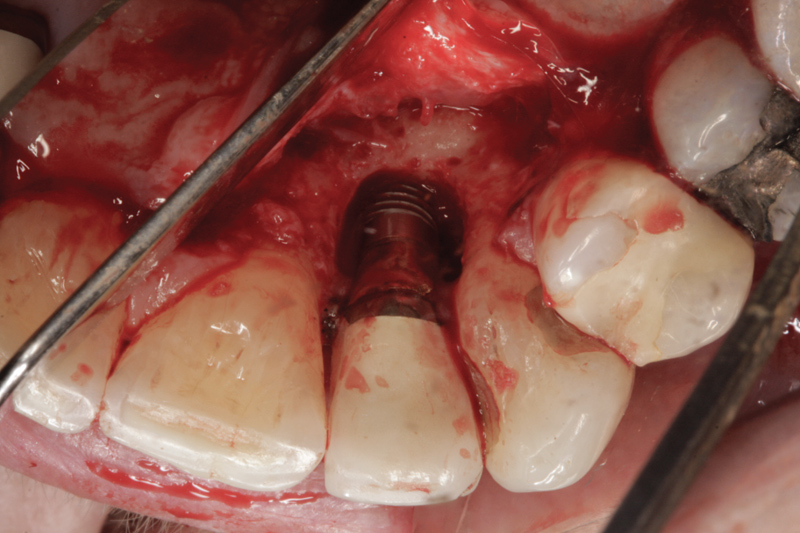

The main biological consideration with cement-retained implant restorations is the vulnerability of peri-implant tissues. Cement contamination readily occurs around implant sites for many reasons. First, as previously mentioned, the soft tissues are much more delicate and vulnerable to tearing when using protection techniques such as retraction cord placement, which is, therefore, contraindicated.16 Cord placement has been shown to strip the weak hemidesmosomal attachment and provide a pathway along the side of the implant for cement extrusion to occur (Figure 1 and Figure 2).17

Second, residual excess cement removal from implants has been shown to be problematic. In 1997 Agar et al showed that even on smooth-surface implant sites, it was not possible to completely remove a resin cement.18 Today’s cements are even more retentive, and the surfaces of implants tend to be purposefully roughened to allow for better healing. Any roughness of an implant or abutment surface must be considered a hindrance to excess cement removal. Retention of any cement remnants may cause an adverse tissue response.

Current Understanding of Peri-implant Disease and Residual Excess Cement

Why implant cement should cause an issue is unclear, as is to what extent the cement plays a part in the process. It is possible that the cement is simply passive and acts as a physical bacterial trap—similar to an overhang on a restoration or calculus effects on the natural dentition (Figure 3). It is also possible that the cement plays a more active role because the destruction of both hard and soft peri-implant tissues is frequently aggressive and extensive (Figure 4 and Figure 5). The disease may be different between patients—and even within the same patient; it may be due to either one major primary factor or a combination of factors.